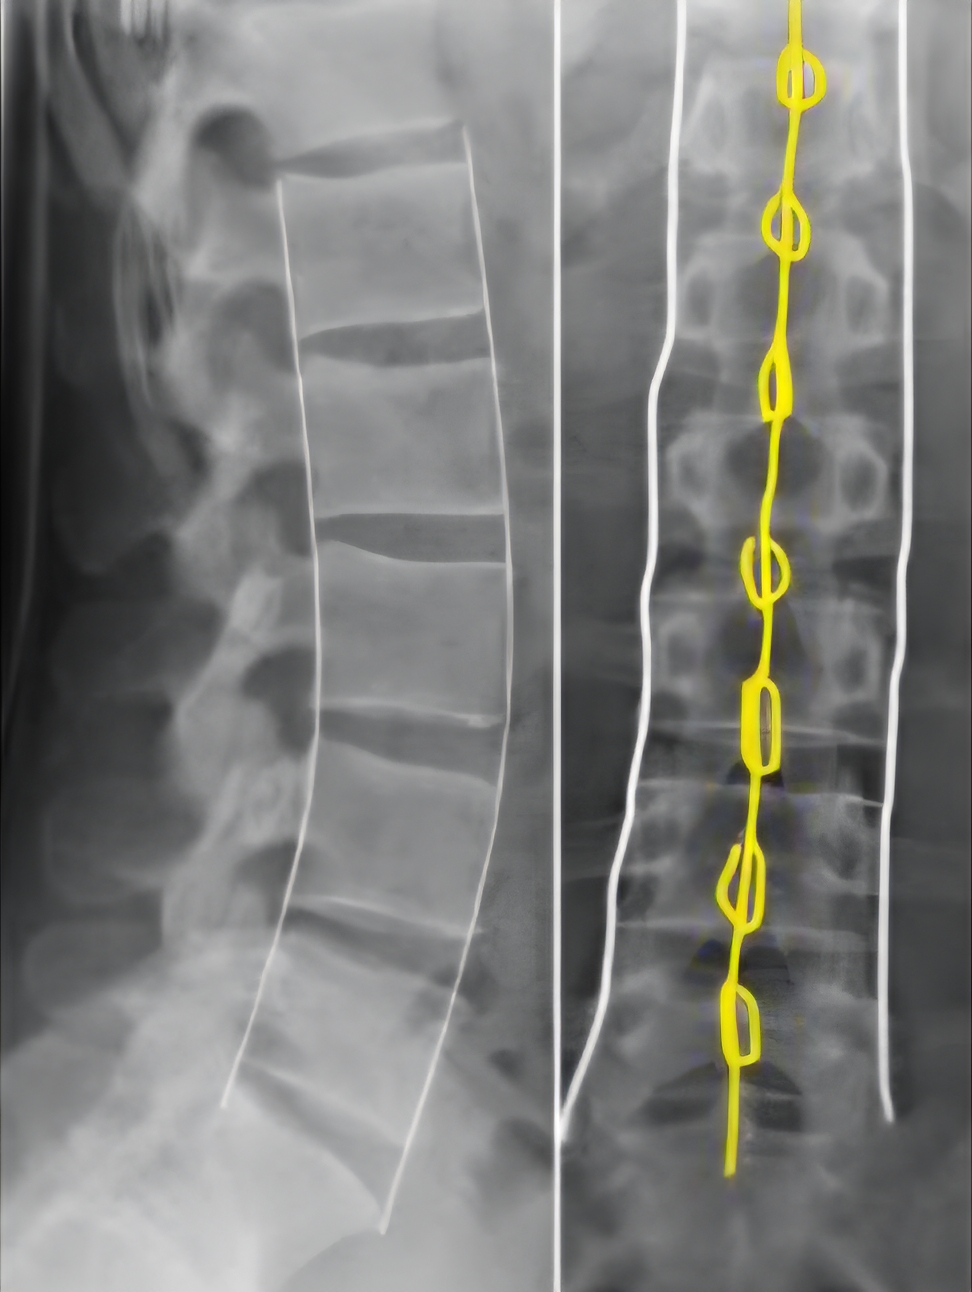

Diagnose

Smerter og palpasjonsømhet/bankeømhet over de aktuelle virvler.

Ved høyenergitraume/ulykker: Undersøk alltid pasienten liggende. Tenk på annen skade (hode/nakke, thorax, bekken, abdomen), sjekk puls og BT.

Spør etter utstrålingssymptomer til underekstremiteter. Nevrologiske utfall? Undersøk sensibilitet, motorikk og reflekser inkludert plantarrefleks.

Røntgen

Front og side + skråbilde overgang cervical.

Rekvirer røntgen thoracal eller thoracal/lumbal-columna. Dersom det er vanskelig å lokalisere smerten eksakt - ta med hele th/l-columna. Når man rekvirerer lumbalcolumna skal man alltid få med de 2-3 nederste thorakale virvlene. Husk at smerten ofte projiseres lenger distalt enn der bruddet er.

Inndeling

Stabile frakturer: < 50 % kompresjon av virvelhøyden, hvor kun 2/3 av virvellegemet er skadet. Pasienter med osteoporose (eldre) kan få kompresjonsfrakturer ved svært lite traume, som regel stabile brudd. På røntgen er det vanskelig å skille mellom nye og gamle brudd (“eskelokk” = fersk fraktur).

Behandling

Mobilisering mot smertegrensen, smertestillende tabletter (obstipasjon forekommer ofte etter brudd i lumbalcolumna og plagene kan forsterkes av Paralgin Forte). Pasienter som ikke kan klare seg hjemme innlegges kirurgisk avdeling (kan pasienten komme til toalettet ved egen hjelp?).

Ved høyenergitraume/fall vurder innleggelse i sykehus for observasjon (kollisjoner eller fall fra høyde over 3 meter).

Instabile frakturer:> 50 % kompresjon av virvelhøyden, alle skader med nevrologiske utfall eller radierende smerter, ryggskader med akseavvik, multitraumatiserte pasienter, skade med kombinert fleksjons/rotasjonstraume eller kraftig traume rett bakfra.

Innlegges nevrokirurgisk avd. UUS. Korrekt leie under transport, informer ambulansepersonell om skaden. Det kan lønne seg å være tilbakeholden med smertestillende medikamenter da avvergeholdning hos pasienten kan beskytte mot forverrelse av skaden.